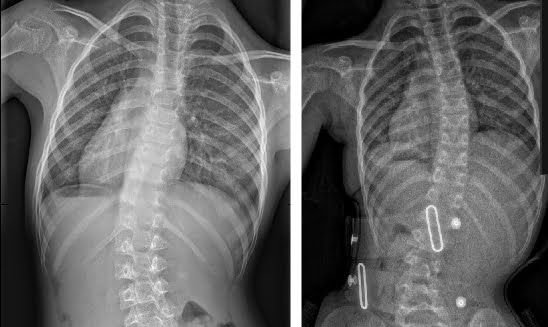

حتى أولئك الذين يعانون من اعوجاج العمود الفقري الشديد، حيث تزيد زاوية كوب عن 40 درجة، فقد استجابوا جيدًا لطريقه العلاج التي تعتمد على أحزمه الجنف تشينو-جينسينجن وبرنامج العلاج الطبيعي الذي يتبع مبادئ العلاج الطبيعي في شروث.

قبل و بعد

قبل و بعد